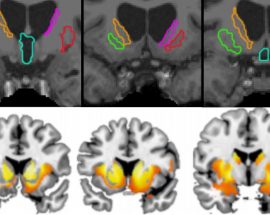

IDIBELL researchers identify a brain region that predicts the evolution of apathy in Huntington’s patients

The atrophy of this region would determine the severity and velocity of apathy development. Apathy is closely linked to the cognitive decline of Huntington’s patients, therefore, this brain vulnerability would help...